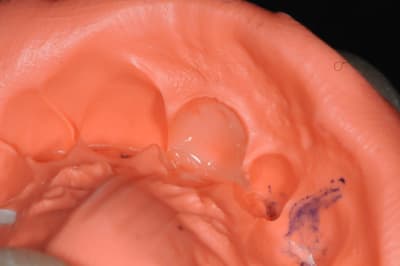

auparavant un isomoulage est effectué avec différentes couches de composite. (la teinte est choisi de mémoire)

1-5 extraction douce au périotome, syndesmotome, davier, clé à molette, etc...

6- aspect externe

7- aspect de l'os

8-11 décolement du périoste de la table externe en passant par l'alvéole

12-15 insertion délicate de la membrane